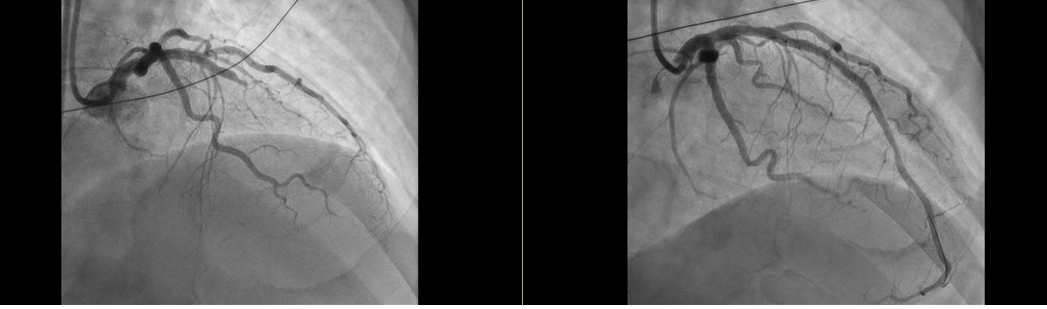

[»çÁø¼³¸í] ÁÂÃø ½Ã¼ú Àü, ¿ìÃø ½Ã¼ú ÈÄ [µ¥Àϸ®¸Þµð ÀÓ¼ö¹Î ±âÀÚ] °æ±âµµÀÇ·á¿ø ÀÌõº´¿ø(º´¿øÀå À̹®Çü)ÀÌ Áö³­ 11ÀÏ ÀÀ±Þ .2020-06-18 09:30:11